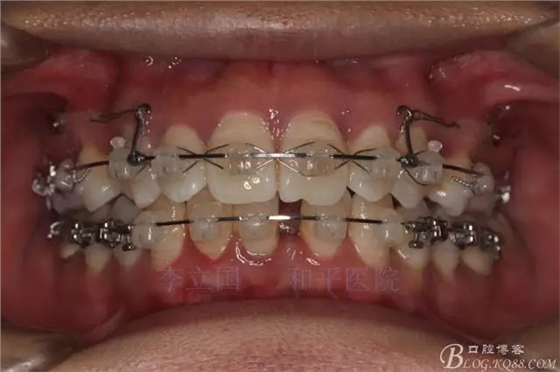

2.Damonclear排齊整平。

3.微種植支抗內(nèi)收上下前牙。

4.調(diào)整咬合關(guān)系。

治療要點(diǎn):

1.患者上前牙直立,面型前突,典型的嘴凸牙不吐,關(guān)鍵是前牙轉(zhuǎn)矩控制,建議使用高轉(zhuǎn)矩托槽。

2.磨牙關(guān)系一側(cè)完全遠(yuǎn)中,一側(cè)遠(yuǎn)中尖対尖,采用兩個(gè)上4,一個(gè)下1的拔牙模式。

3.上頜應(yīng)用支抗釘。表麻下在56牙槽間隔植入,注意因使用的為鈦合金釘,一直保持植入角度與骨面成60度角,不要垂直植入再改變角度。要求即刻加載,即刻加載力值2盎司。

4.使用長(zhǎng)牽引鉤,使?fàn)恳咏项M骨阻抗中心,防止上頜骨的順時(shí)針旋轉(zhuǎn)。

5.回收過程中,上下前牙輕搖椅,防止覆合加深。